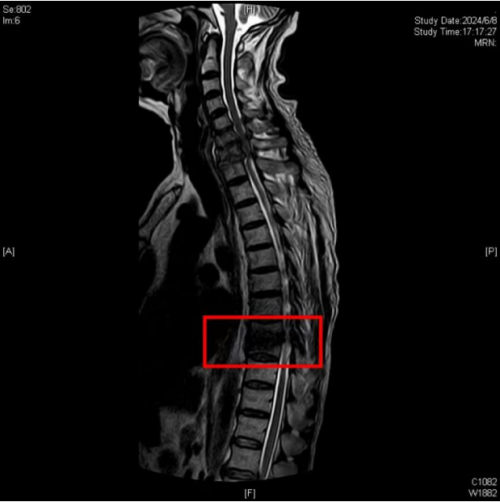

谭松入院后,经过相关检查后诊断为:“脊柱结核性截瘫(颈,胸,腰椎),胸椎多处骨质破坏,椎旁脓肿形成,肝肾功能不全、高血压、糖尿病、贫血、低蛋白血症、多处压疮”。患者的病情不容延误,脊柱二区曾浩主任迅速带领医护团队为其制定了个性化手术方案,邀请了麻醉科、心内科、内分泌科、输血科多学科会诊讨论,最终决定实施“胸椎后路结核病灶清除、椎管减压、椎间骨柱植骨融合、钉棒系统内固定术”。手术顺利,术后病情稳定,继续行抗结核治疗及营养支持、皮肤护理等对症治疗。

术前,CT检查示胸椎多处骨质破坏,椎旁脓肿形成